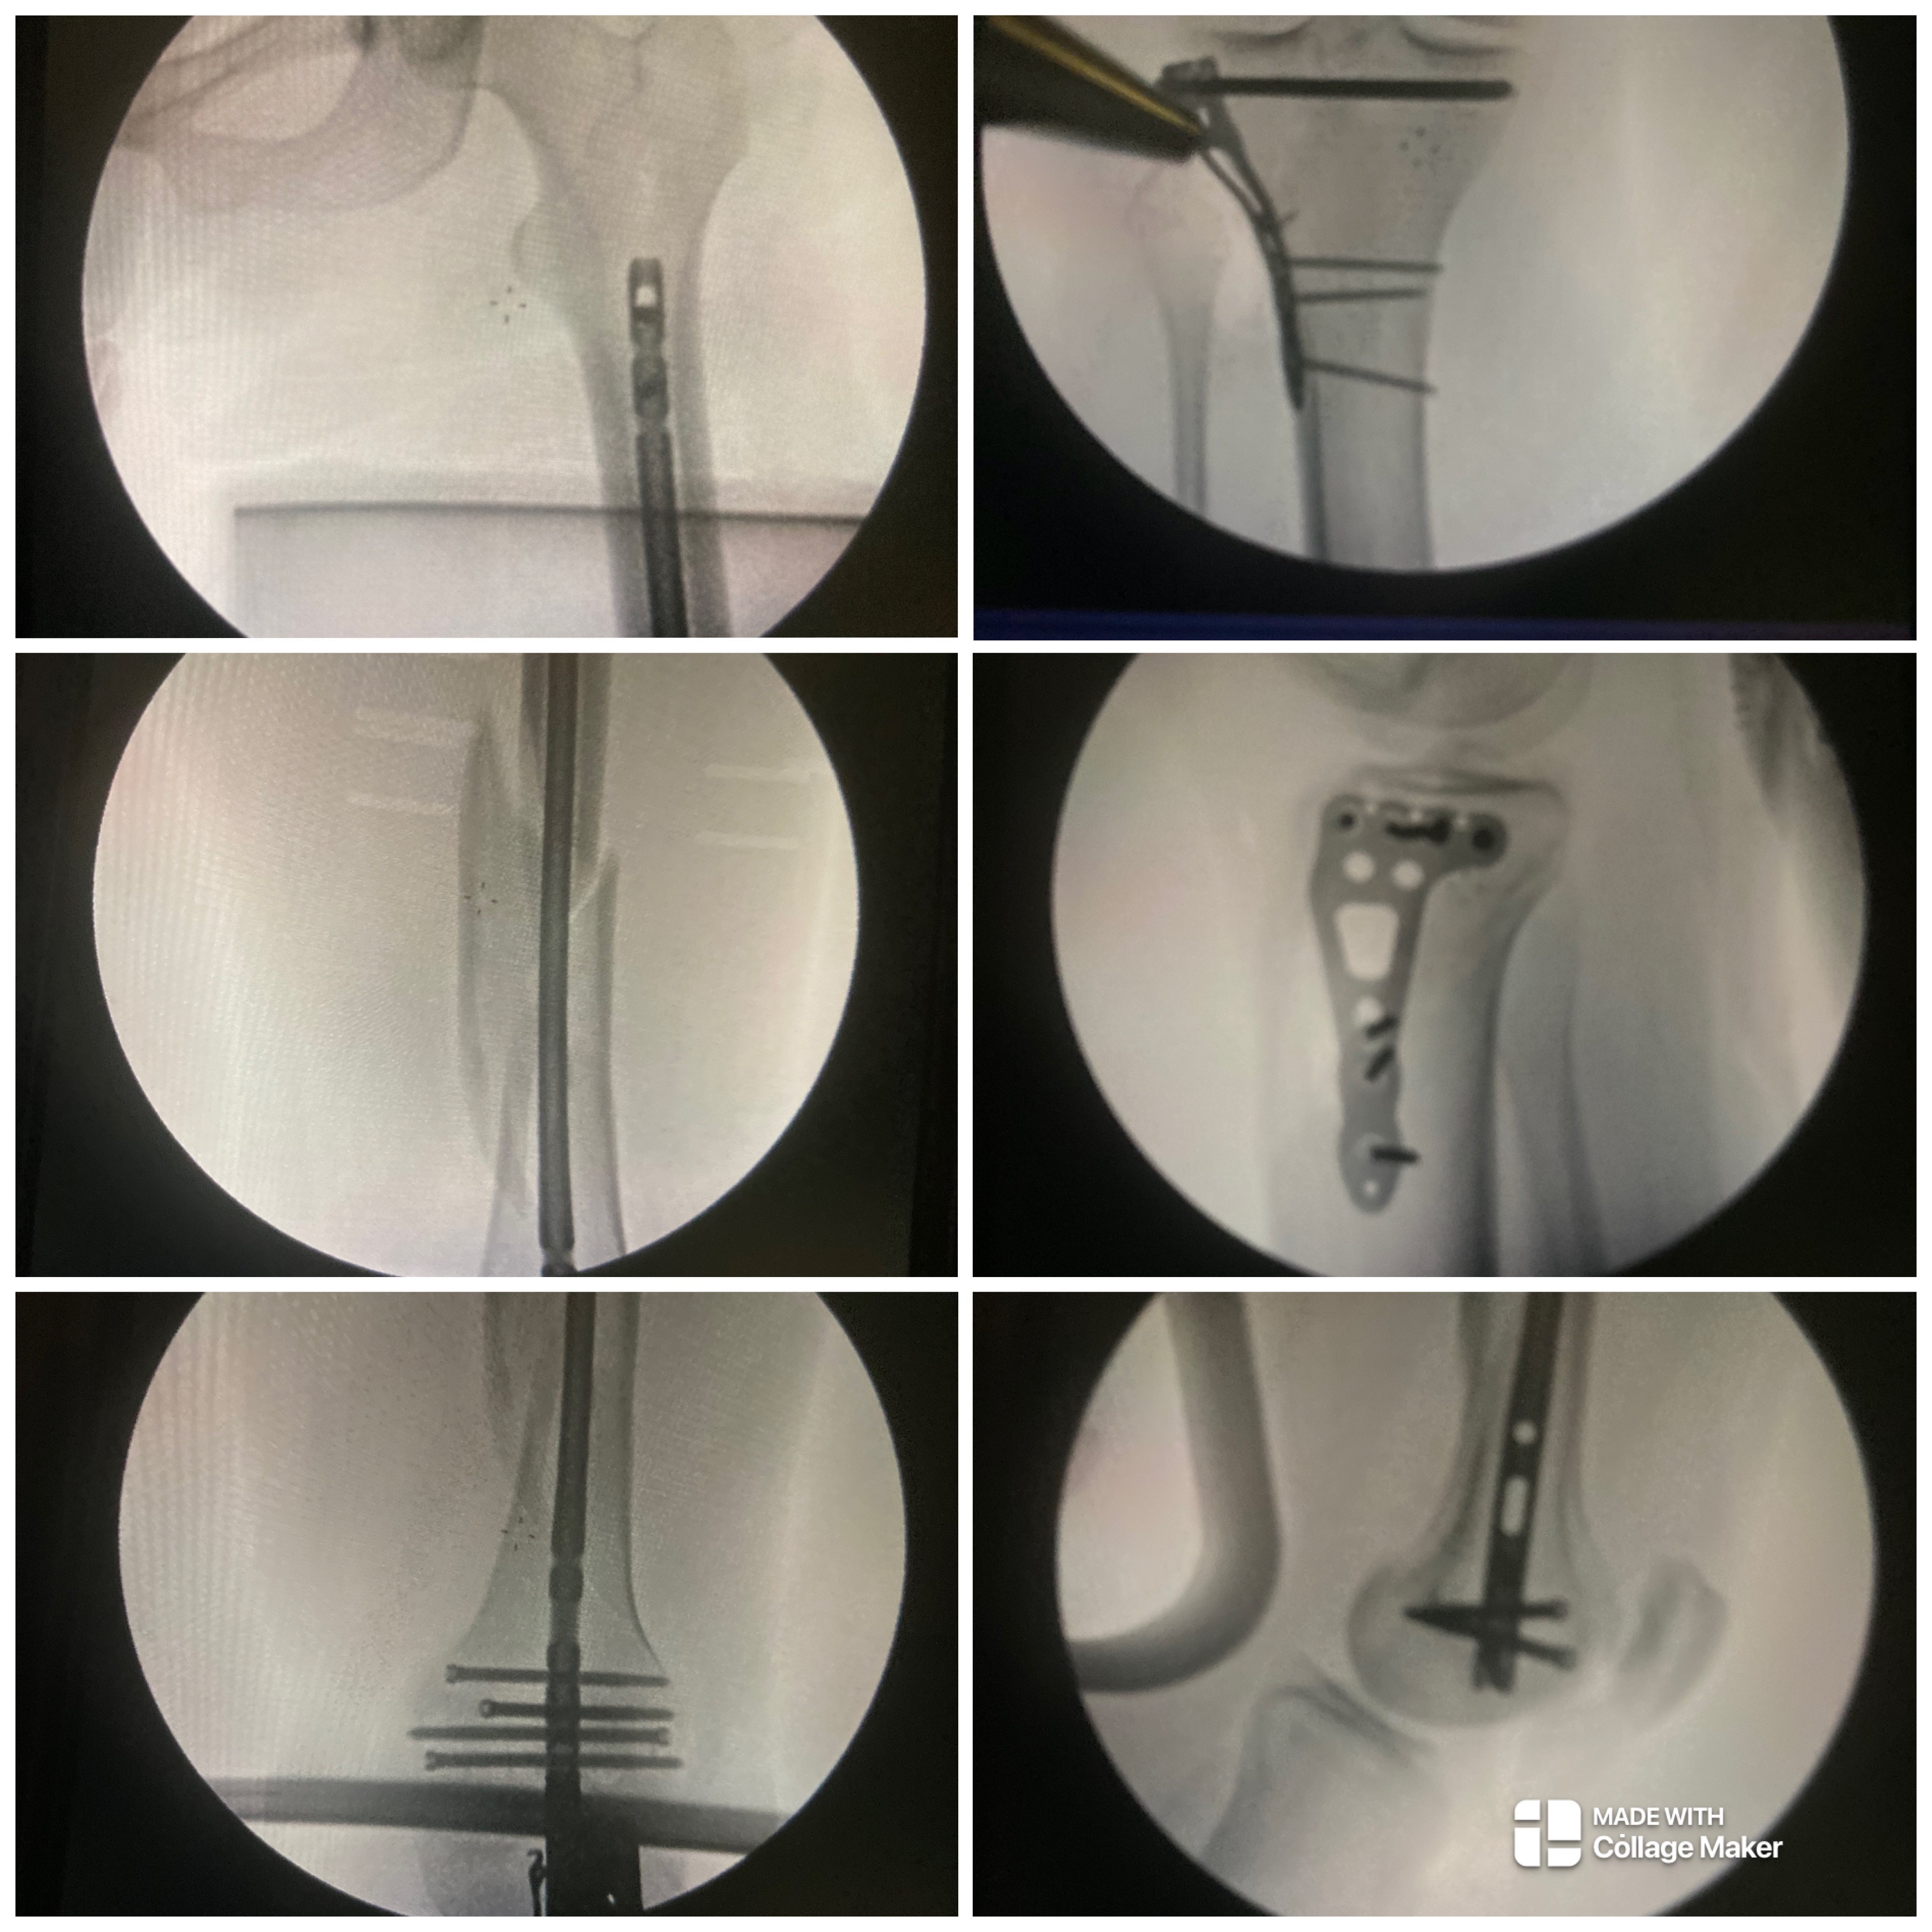

My little brother, Jon’s life changed in an instant when he was riding his motorcycle and was hit head-on by someone who ignored the right of way and cut directly in front of him. The impact left Jon with two broken legs that required rods, plates, and screws, a deep cut down his face that needed stitches, and a broken right wrist. The physical pain has been overwhelming for Jon, and the emotional and financial challenges have been just as tough for him.